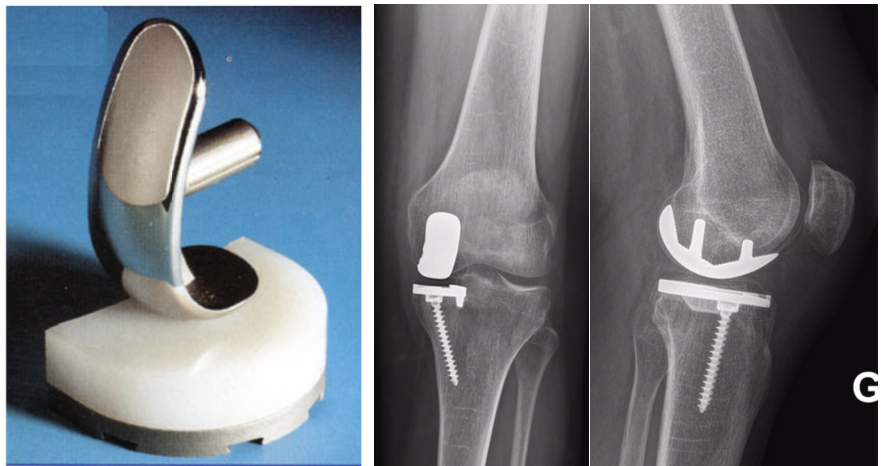

A la différence d’une prothèse totale de genou qui remplace toute l’articulation du genou usée dans sa globalité, une prothèse partielle du genou s’adresse à une usure localisée d’un des 3 compartiments du genou.

Il est donc possible de remplacer le compartiment fémoro-tibial interne, le compartiment fémoro-tibial externe et le compartiment fémoro-patellaire.

La chirurgie est réalisée sous anesthésie générale, rachianesthésie ou locorégionale. En cas de prothèse unicompartimentale interne (PUC interne), nous réalisons une voie d’abord chirurgicale antéro-interne courte de l’ordre de 7 à 10 cm partant du relief du bord supéro-interne de la rotule jusqu’au bord supéro-intern de la tubérosité tibiale antérieure. En cas de PUC externe nous réalisons inversement une voie d’abord chirurgicale antéro-externe partant du relief du bord supéro-externe de la rotule jusqu’au bord supéro-externe de la tubérosité tibiale antérieure. Dans les 2 cas l’articulation est ouverte le long du tendon rotulien et après mise en place des écarteurs chirurgicaux les surfaces articulaires du fémur et du tibia sont exposées. Nous mettons alors en place les guides de coupes osseuses puis préparons les surfaces osseuses à accueillir la prothèse.

Après vérification finale la prothèse définitive est implantée fixée dans l'os par impaction (prothèse sans ciment) ou avec du ciment (prothèse cimentée) au libre choix de votre chirurgien. A la fin de l'intervention, un drain est souvent mis en place permettant d'évacuer l'hématome. En cas d’implantation d’une prothèse unicompartimentale fémoro-patellaire, la voie d’abord chirurgicale est un petit peu plus grande et s’apparente à une voie d’abord de prothèse totale de genou.